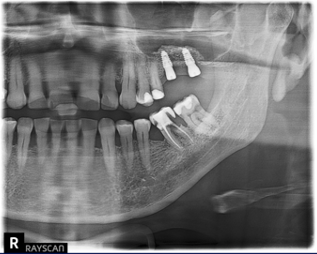

Today's modern implant systems differ greatly from their predecessors and are now also strongly dependent on their range of indications. Here, requirements such as immediate implantation, placement in different bone qualities and behavior in relation to soft and hard tissue must be taken into account. In addition, there are also modern types of reconstructions such as immediate temporization, the all-on-x concept or the possibility of the integration into the digital workflow.

This lecture will go into all the points mentioned above, present and explain them using an implant system as an example. The focus is on the presentation of the biological components, which are important for an implant system of today both for short-term success with immediate implantation and immediate restoration as well as for long-term success through the stability of the surrounding tissue structures.